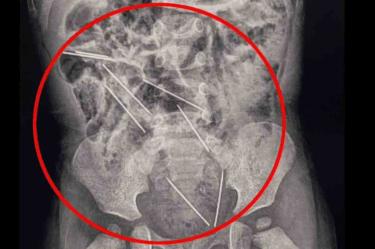

La mamá del pequeño se percató de lo ocurrido, por lo que de inmediato fue llevado al hospital en donde fue sometido a una exploración, en donde las radiografías mostraron que las agujas estaban dentro del sistema digestivo del niño.

Algunas de estas, se encontraban muy cerca de los órganos vitales del bebé, por lo que de inmediato los médicos lo sometieron a una cirugía de casi dos horas para retirar las agujas, y también recibió tratamiento por una pequeña lesión en el intestino delgado. Después de varios días en el hospital, se le dio de alta.